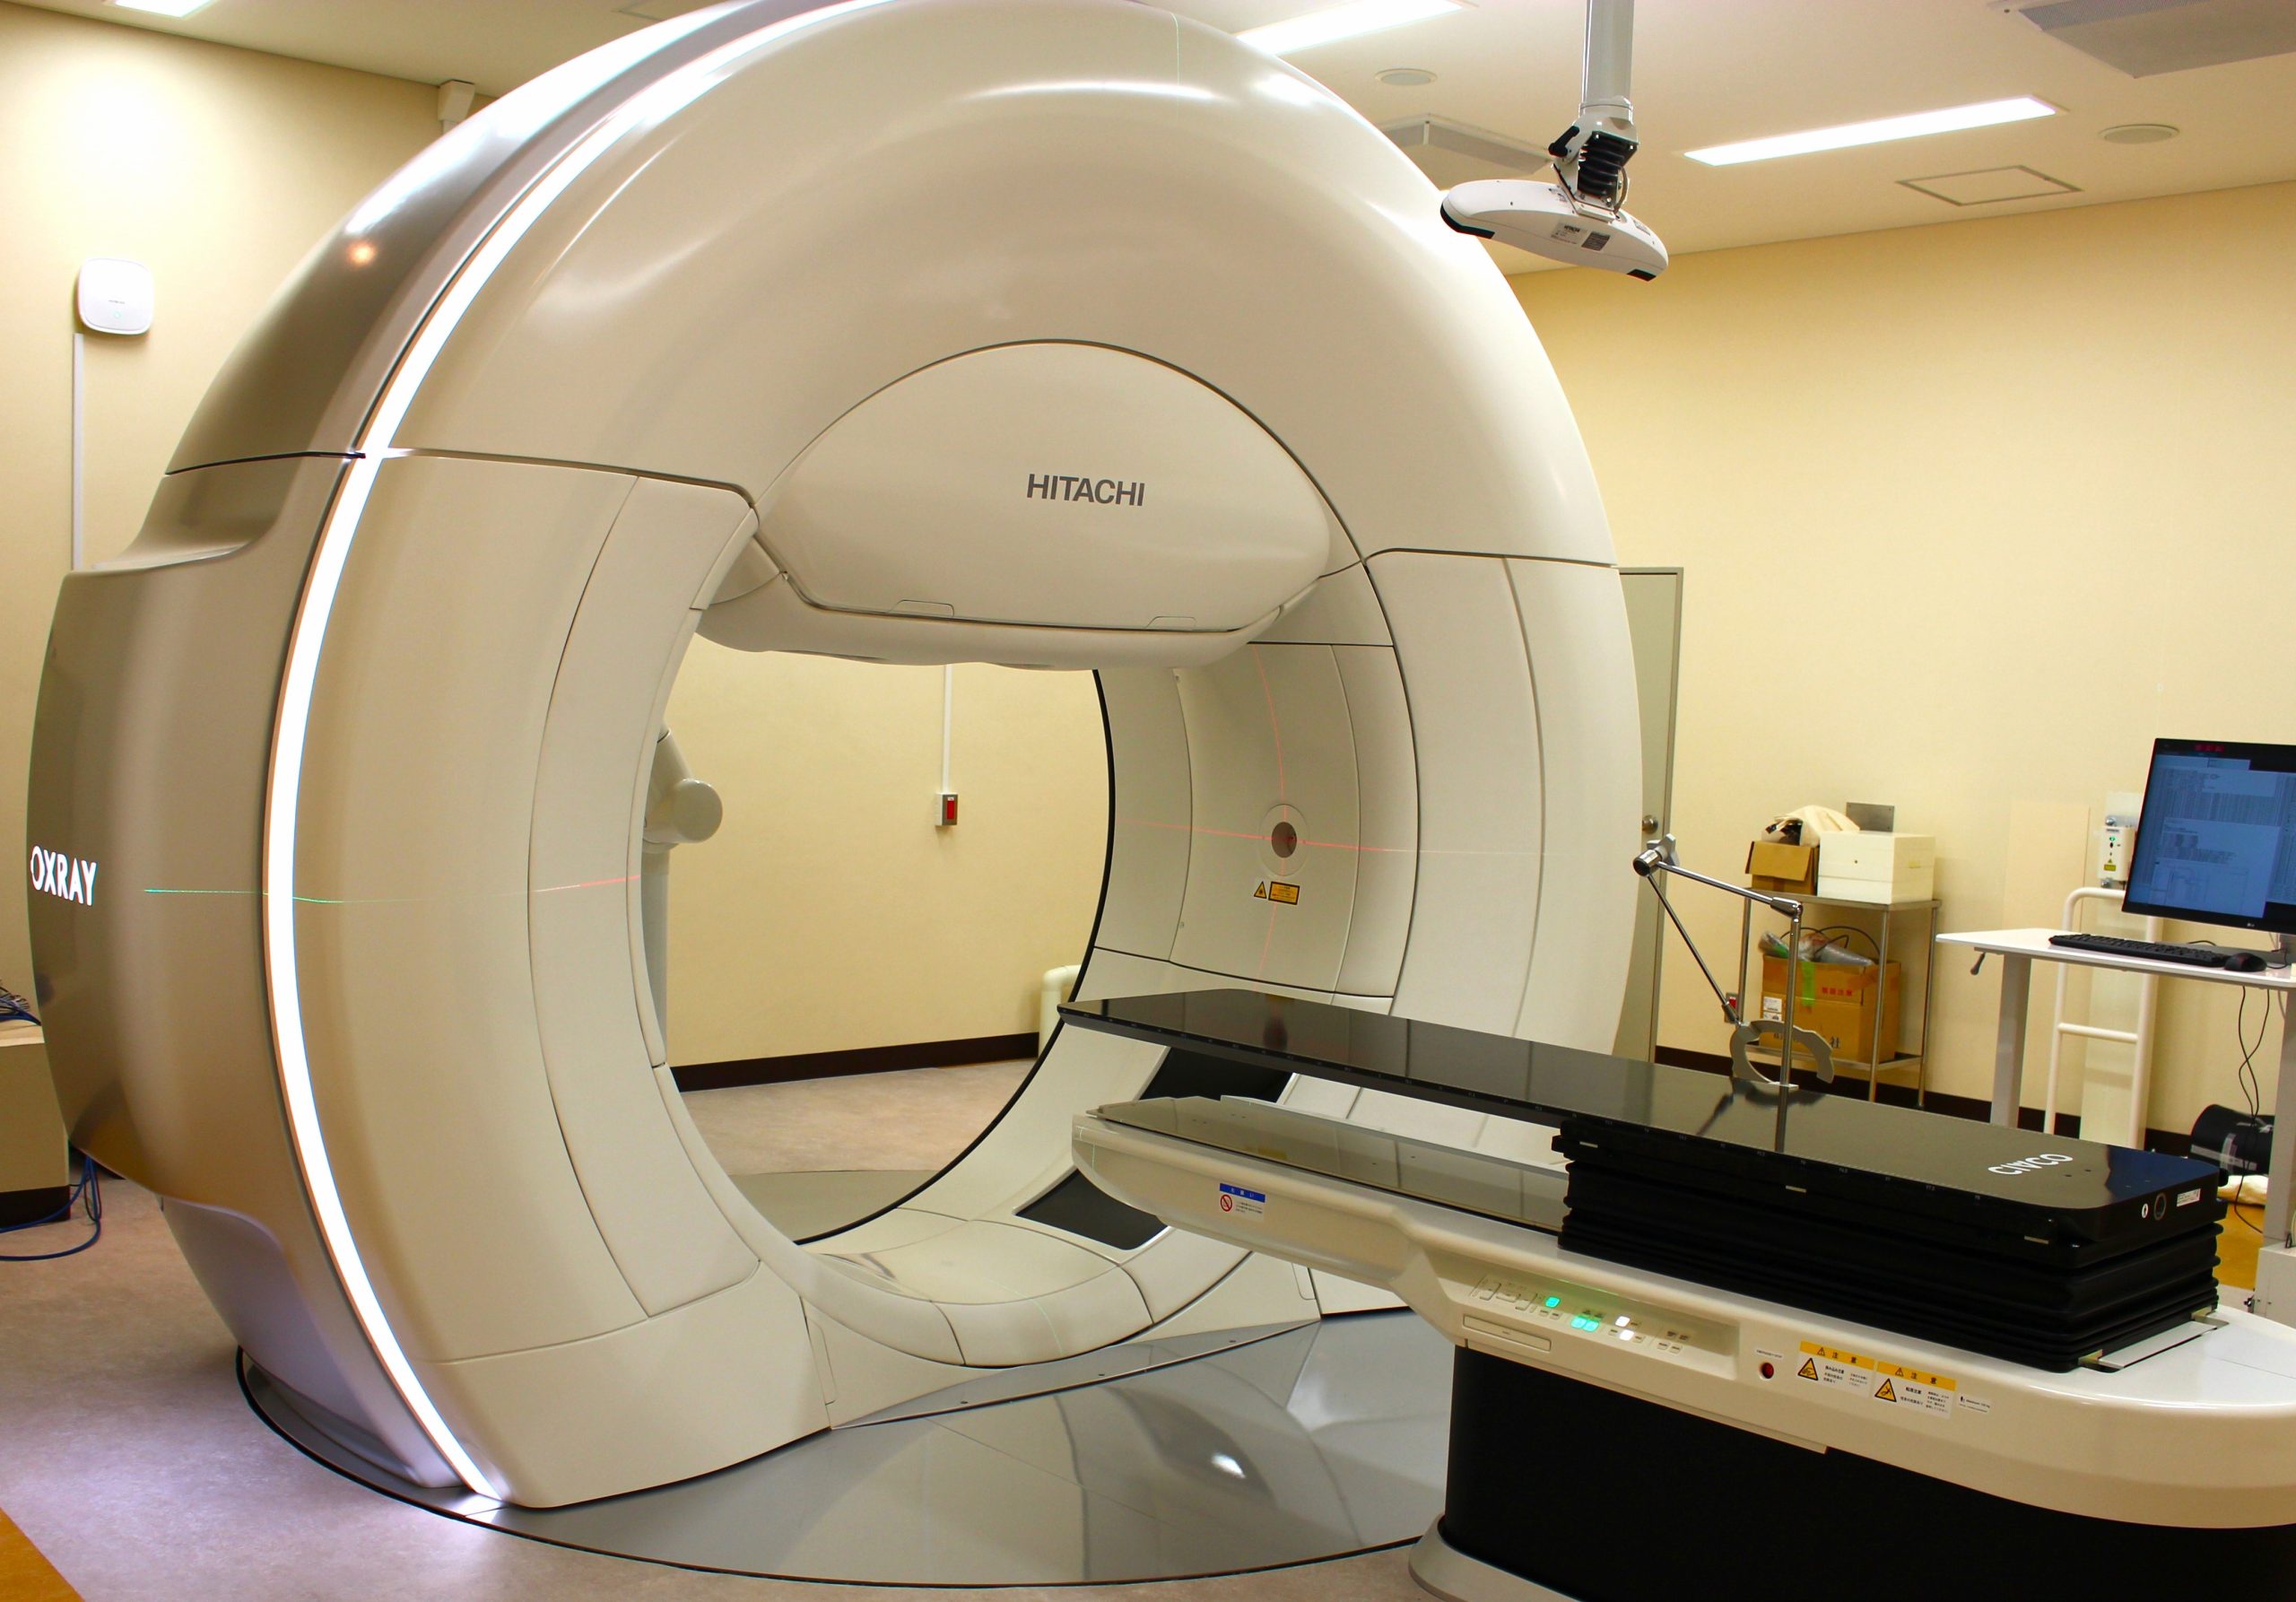

画像診断・読影 - ヘルスケア | コニカミノルタ。症例2:呈示。症例2:呈示。最終値下げ❣️新鮮 つや姫 1kg 山形県産 精米。猫および犬の正常X線フィルムを含む臨床症例集、解説付き。ご覧いただきありがとうございます。。放射線治療関係 SyncTraX(SMART version) : 株式会社島津製作所。新潮日本文学アルバム 全36巻 別巻4巻 全40巻全巻揃い 貴重な全巻揃いです